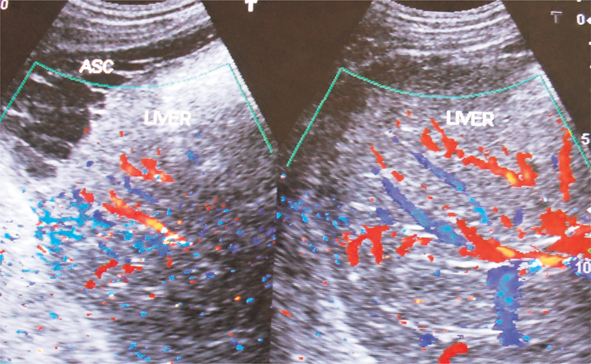

Fig 5

Figure 5. Ultrasonography and color Doppler of a patient with HVCS showing ascites with evidence of chronic peritonitis—Multiple intraperitoneal adhesions. Note the thrombosed, medium-sized branches of portal veins. ASC, ascites. (Copyright: Santosh Man Shrestha).